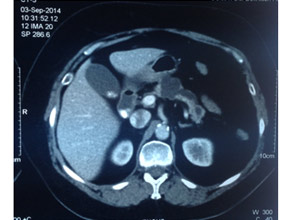

CT scan of pancreatic cancer in the body

Large Neuroendocrine tumour in pancreatic head